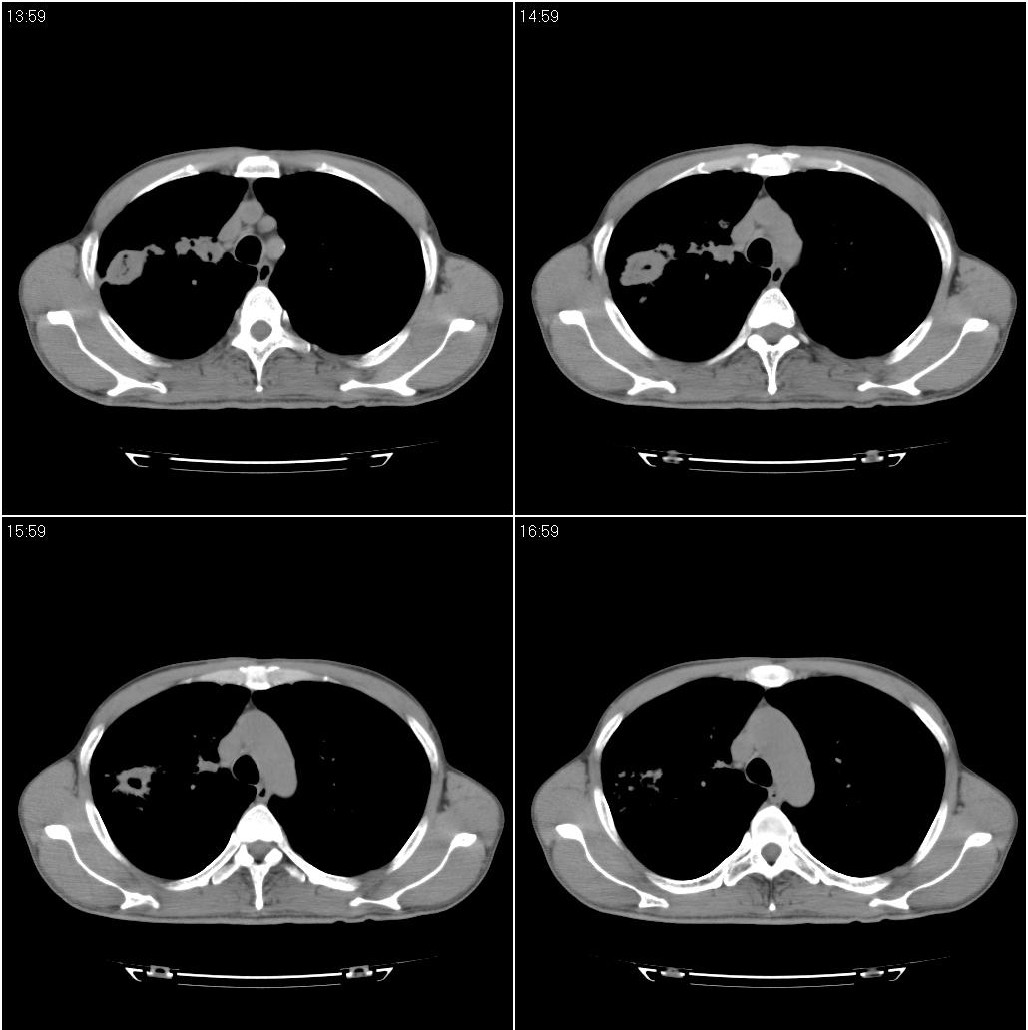

两肺继发性肺结核并多发性结核球形成,部分病灶内空洞形成。

两肺继发性肺结核并多发性结核球形成,部分病灶内空洞形成。支持

两肺继发性肺结核并多发性结核球形成,部分病灶内空洞形成

符合继发性结核表现部分空洞形成并播散